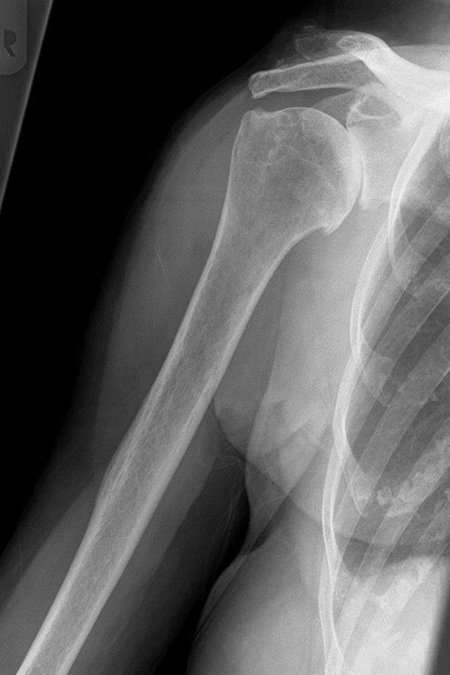

Die Erkrankung der Sehnen kann von einer Aufrauhung über eine Teildurchtrennung bis hin zum vollständigen Abriss der Sehnen reichen. Durch eine klinische Untersuchung mit spezifischen Funktionstests zur Beweglichkeit und Kraft sowie bildgebenden Untersuchungen wie Röntgen, Ultraschall und Kernspintomographie kann ein genaues Gesamtbild der Situation im Rahmen der Sprechstunde erstellt werden.

Bei fortgeschrittenem Sehnendefekt kommt es zum Höhertreten des Oberarmkopfes unter das Schulterdach. Die dauerhafte Dezentrierung führt zu einem speziellen Bild des Gelenkverschleißes (Defektarthropathie). In solchen Fällen können künstliche Schultergelenke sehr hilfreich eingesetzt werden.

ROTATORENMANSCHETTENMASSENRUPTUR

Rotatorenmanschettemassenruptur: Subscapularis- und Infraspinatus-Abriss

Rotatorenmanschettemassenruptur: Supraspinatusabriss

Rotatorenmanschettemassenruptur: teils offene transossäre Auszugsnähte mit Fixation über Plättchen